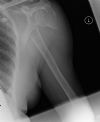

Proximal humeral fracture - AP view (2)